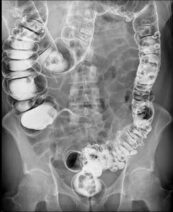

Radiografías del tracto gastrointestinal inferior (enema de bario): se puede restringir su alimentación durante algunos días antes del estudio. Se usan laxantes, enemas, o ambos, para vaciar el intestino grueso. Para el estudio, usted se acuesta y será sujetado a una mesa. Se toma una serie de radiografías. Luego el líquido de bario se coloca dentro del intestino por medio de un tubo pequeño y blando ubicado en el recto. El líquido se siente frío. Se procede a tomar más imágenes mientras la mesa le inclina a usted en diferentes posiciones. Esto ayuda a que el bario se mueva por los intestinos de modo que puedan verse en las radiografías. Tiene que permanecer acostado inmóvil y contener la respiración cuando se toma cada imagen.

Después del estudio, puede ir al baño para eliminar la solución de bario de los intestinos. (Pueden pasar varios días hasta que esta se haya eliminado por completo. Sus deposiciones pueden ser más secas, más duras y de color claro durante este tiempo).

Para obtener imágenes más claras, por lo general se realiza un examen con “contraste doble”. En este examen se usa una cantidad más pequeña de líquido de bario más espeso. Después que el bario está adentro, se hace ingresar aire en sus intestinos. Esto puede causar una sensación de hinchazón y malestar, junto con la ganas de vaciar los intestinos.